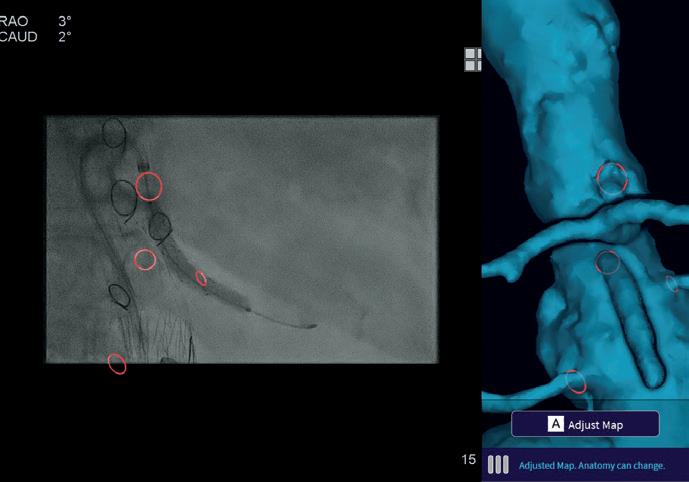

The patient returned two weeks later for his PMEG EVAR. The PMEG was created with a Zenith dissection endovascular graft (ZDEG; Cook Medical) 32x24x158mm with four-vessel direction branches with Viabahn (Gore) stent grafts. Cydar technology was of paramount importance in attaining the proper alignment of the endograft fenestrations with the correct visceral orifices (Figure 2). The visceral cannulations and stent deployment were performed from femoral access with the Nagare Steerable sheath (Terumo). Cydar technology aided in proper alignment, cannulation and stent deployment of the directional branches (Figure 3). Viabhan VBX (Gore) stents were delivered as branch extenders without difficulty into the right renal artery (6x59mm), superior mesenteric artery (8x59mm and 8x39mm) and celiac artery (8x59mm and 8x39mm). Due to acute tortuous angulation, we had a difficult time with cannulation and stent delivery in the left renal artery. However, after a period of time, a Viabhan (7x50mm) and VBX (6x59mm) stent were deployed and extended

the directional branch into the left renal artery. The Nagare Steerable sheath was able to perform the visceral cannulations via the femoral access, and upper-extremity access was not needed. Cydar software aided the proper alignment of the Nagare sheath with the fenestration and visceral orifice, making the cannulations feasible. The patient had an uncomplicated course and was discharged on postoperative day four.

Intraoperatively, the fluoroscopy time was 83.1 minutes, half-strength contrast of 246ml Visipaque (GE Healthcare) was used, total air kerma (AK) was 5423mGy, and dose area product 727Gycm2. For this case,

technology aided in proper alignment, cannulation, and stent deployment of the directional branches

Figure 2. Alignment of the endograft fenestrations with the correct visceral orifices using Cydar technology

Figure 3. Cydar